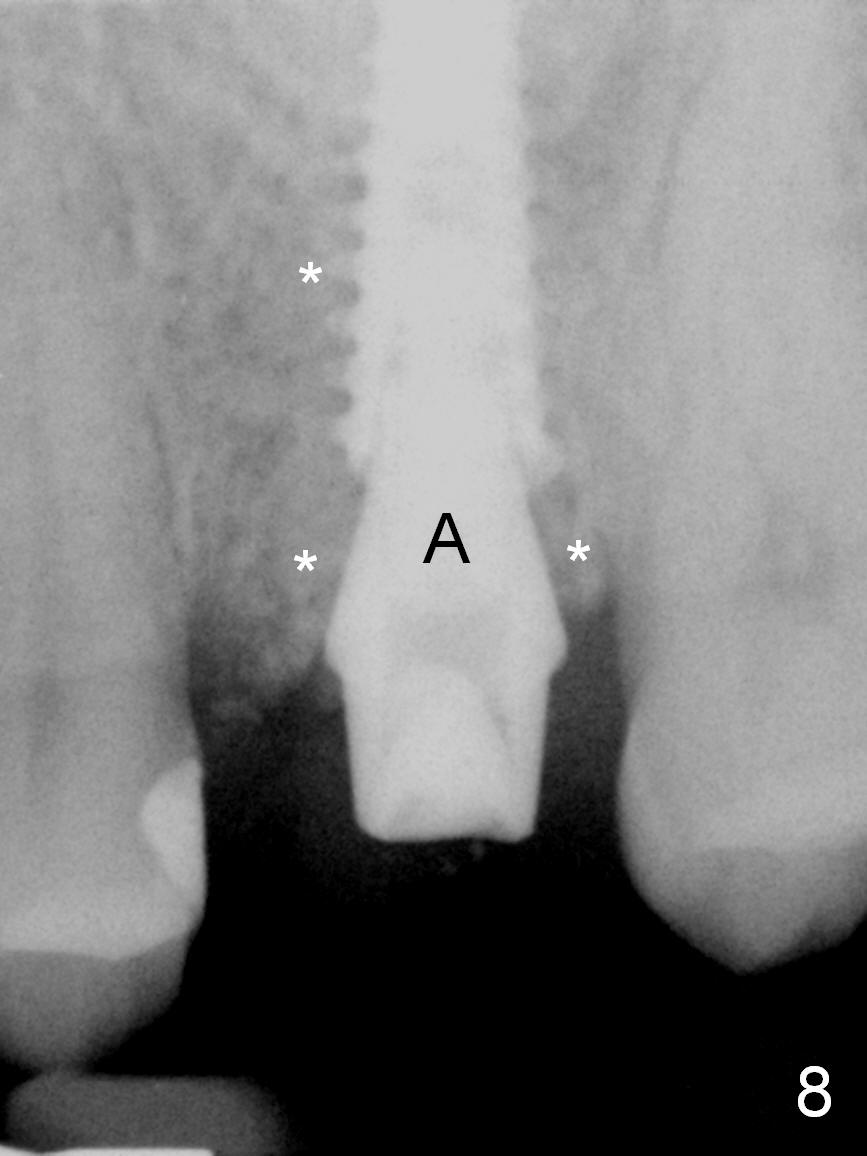

The septal bone is dense and the osteotomy is enlarged by alternating use of drills and expanders. By the time 3.8 mm ME is tapped in (Fig.6), the buccal plate of the septum is perforated. The ME is stable, in spite of the fact that it is only supported by 2-3 mm bone buccally (Fig.7). Continuously alternating use of MEs and drills leads to placement of a 5x11 mm implant with 30 Ncm insertion torque and sinus lift. After placement of bone graft (Fig.8 *) and 5x4(3) mm pair abutment (A), an immediate provisional is fabricated. Red dashed lines in Fig.6,9 represent the mesial outline of the socket, whereas black dashed in Fig.6 sinus floor. It suggests that the implant is stabilized by relatively small amount of native bone. Although IBS implants have aggressive thread patterns, a proper apical osteotomy should be prepared in the depth (perforates the sinus floor in this case) and diameter (4.3 mm drill) prior to placement.